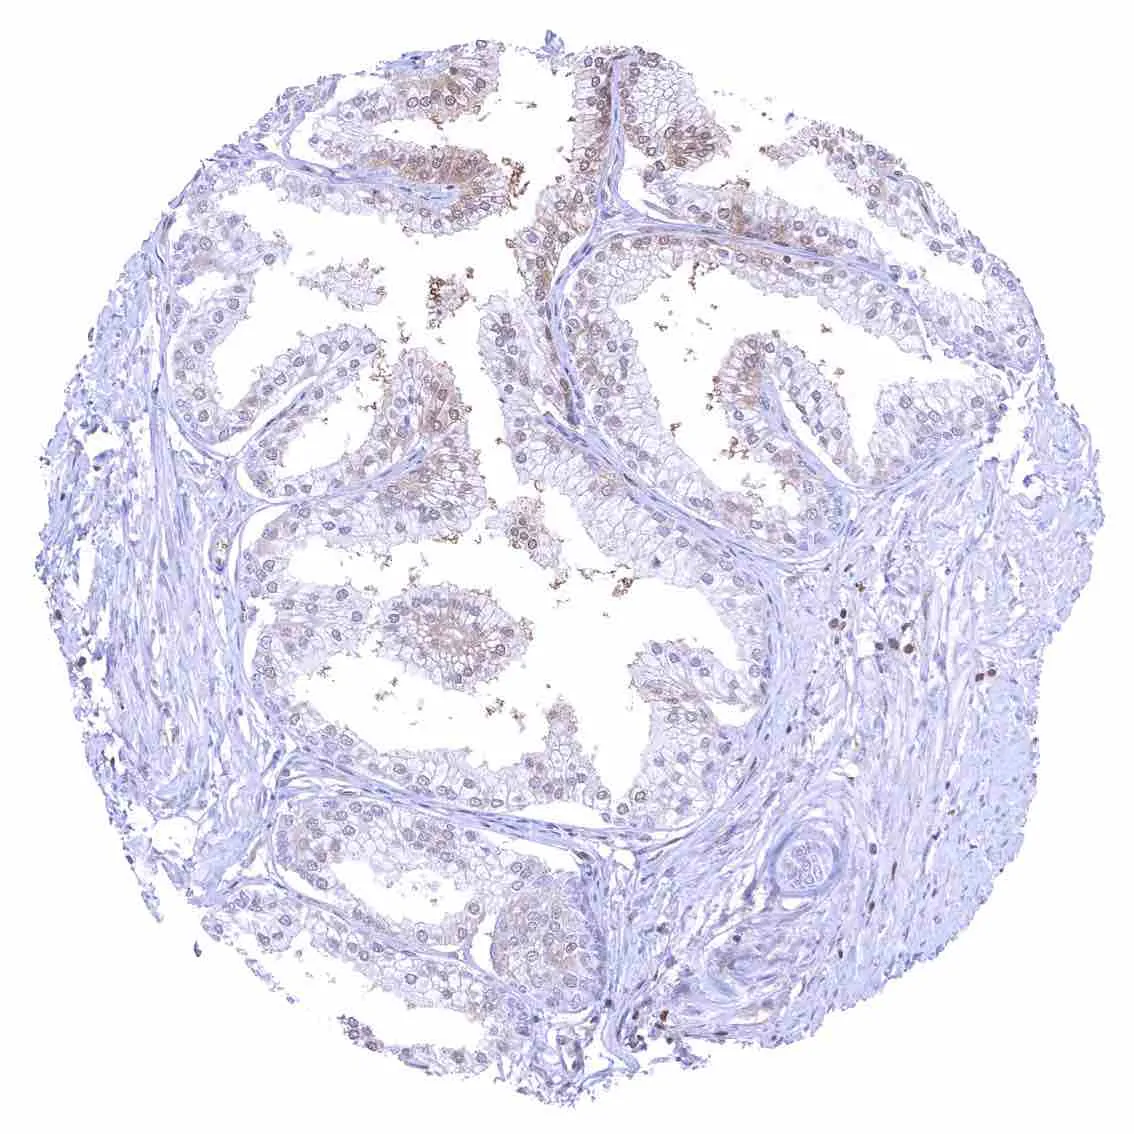

Placenta, early – Strong p27 staining of all nuclei of the syncytiotrophoblast.